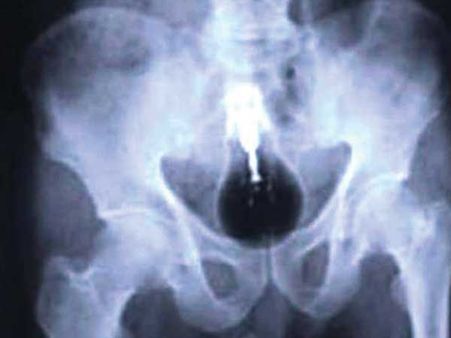

চাবি

মদ্যপ অবস্থায় ১৮ বছরের এক কম্পিউটার ডিজাইনার নিজের বাড়ির চাবি গিলে খেয়েছিল। ৩১ ঘন্টা পরে মূত্রের সঙ্গে চাবিটি তার শরীর থেকে বেরিয়েছিল।